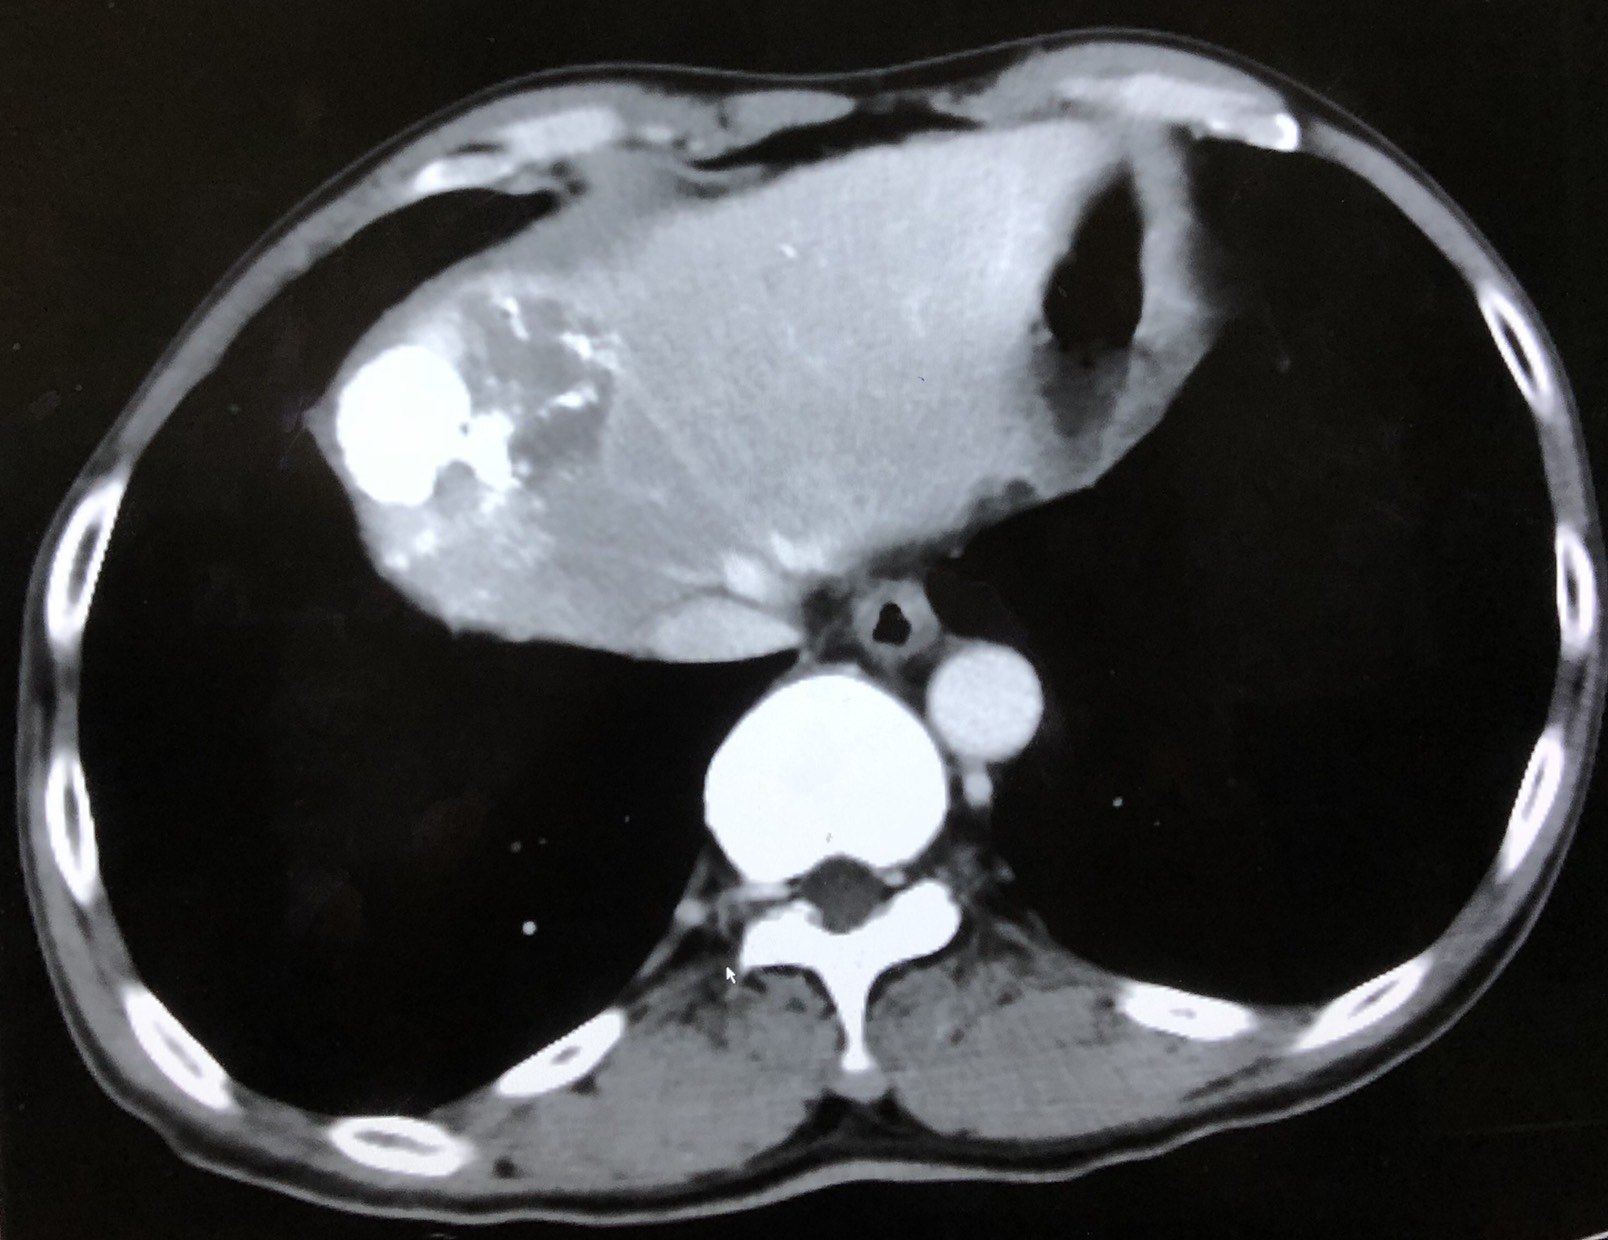

氩氦刀冷冻消融治疗膈顶肝癌案例分享 - 好大夫在线

第8胸椎体,三腔心,右膈顶的层面

ppt腹部横切面断层示意图-解剖图片肝脏,膈顶层面女性轴位断层标本(1)